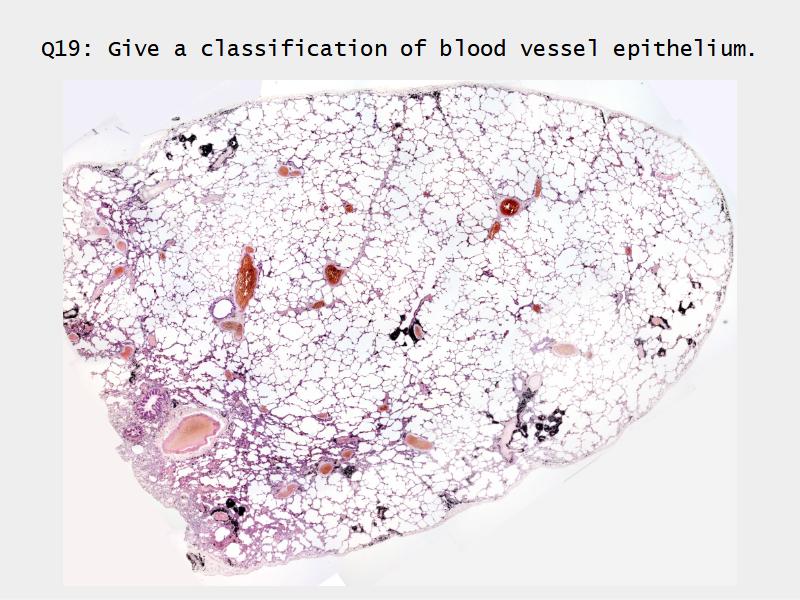

Slides: Respiratory System

- Slide 72 & 74: Lung

Lungs